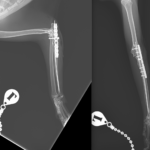

猫ちゃんがお家から居なくなり、探していたところお庭でうずくまって居るところを発見されました。かかりつけの動物病院で両側のモンテジア骨折と診断されました。(原因は落下事故と判明)外科的整復のため当院へ搬送されました。橈骨頭を整復したのち、尺骨にIM pinを刺入、2.0-Locking Plateで固定術を行いました。橈骨頭へ尺骨側からポジションスクリューで固定を併用します。このスクリューは約4週間を目安に抜釘を予定しています。